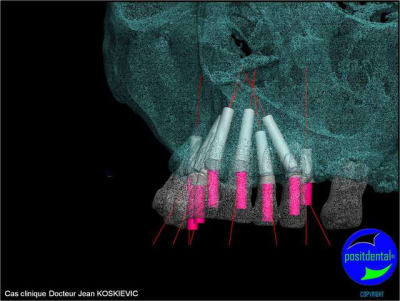

et la projet 10 implants maxillaire sup

et là béotien ?

10 en haut